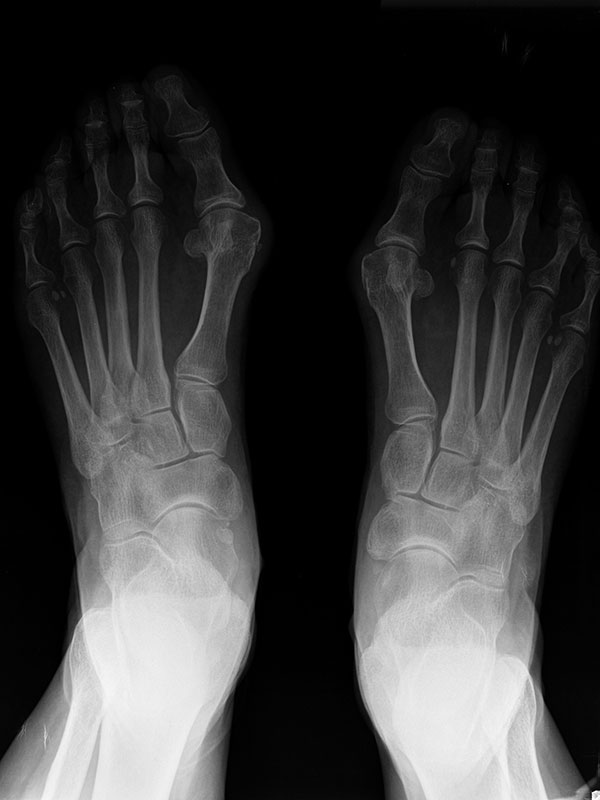

En el hallux valgus y en las fases incipientes del hallux rigidus fijamos la corrección deseada con tornillos (cirugía percutánea de 3ª generación) lo que confiere más estabilidad y por tanto nos permite conseguir unas mayores correcciones de la deformidad sin apenas dolor respecto a otras técnicas percutáneas.

Antes